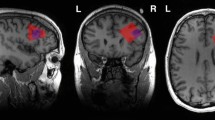

Functional coupling of regional cerebral metabolic rates for glucose measured with [18F]-Fluoro-2-deoxy-D-glucose PET was compared in 18 drug-free patients with Tourette's Syndrome (TS) and 16 age- and sex-matched control subjects. Pearson product-moment correlation matrices containing correlations between metabolic rates in regions sampled throughout the brain were generated independently for TS patients and controls and compared. Significant differences between Z-transformed correlation coefficients were used to identify group differences, and revealed that the connectivity of the ventral striatum was most severely affected in TS. Changes in the coupling of other brain areas—primary motor areas, somatosensory association areas, and insula—also appeared to differentiate TS patients and controls. Evaluation of interrelationships between cortico-striato-thalamo-cortical circuits revealed the existence of functional connections between the motor and lateral orbitofrontal circuits in both groups, however, a reversal in the pattern of these interactions differentiated TS patients and controls. In controls, activity in these circuits appeared to be negatively correlated —i.e. increased activity in one is associated with relative inactivity the other. In TS patients, on the other hand, activity in the motor and lateral orbitofrontal circuits appears to be positively coupled. These results lend further credence to the hypothesis that altered limbic-motor interactions represent a pathophysiological hallmark of this disease.

We have previously reported (Braun et al. 1993, 1995) that TS may be characterized by lower metabolic rates in discrete portions of inferior limbic cortex and striatum, and in subcortical limbic structures, and higher metabolic rates in the superior sensorimotor cortices. However, brain regions do not operate in isolation; they function as elements in a series of neural networks distributed throughout the central nervous system, and it is likely that abnormal functional relationships between these regions play a role in the pathophysiology of TS. Positron emission tomography (PET) data can be analyzed using statistical methods that attempt to identify these regional interrelationships. That is, correlations between regional metabolic rates for glucose can be used to characterize networks of regions that appear to be affected in a neuropsychiatric disease, and, potentially, to pinpoint a breakdown of organized transynaptic activity which might distinguish the disorder (Clark et al. 1984; Horwitz et al. 1984, 1991).

The purpose of the present study is to determine how the functional interactions between brain regions are altered in TS—information that may shed light on system level abnormalities in this disease. We describe a 3-step analysis performed on [18F]-Fluoro-2-deoxy-D-glucose PET data acquired in TS patients and normal volunteers. The first stage constitutes a global analysis in which all interregional correlations between brain regions found to be significant in our first publication (Braun et al. 1993) are compared in order to identify those regions in which disordered functional interrelationships best characterize TS patients. The second step involves the generation and analysis of brain maps depicting interactions between specific brain regions and the rest of the brain—the specific brain regions were chosen based on the results of our previous work and their likelihood to play a role in TS. The third step involves the evaluation of functional interactions between elements of cortico-striato-thalamo-cortical (CSTC) circuits, initially described by Alexander et al. (1986), in order to identify potential sites at which abnormal limbic-motor interactions may occur.

PET scans were performed as described previously (Braun et al. 1993). Five mCi of [18F]-Fluoro-2-deoxy-D-glucose (FDG), was injected intravenously over a period of one minute. Ten-minute scans were initiated 30–45 min after injection of FDG. Local cerebral metabolic rates for glucose (CMRglu) were calculated according to the method of Brooks (1982). Planes of section were selected for analysis and regions of interest (ROI) were placed to sample normalized CMRglu. Names and locations of all regions sampled were tabulated in the first publication (Braun et al. 1993). Regional CMRglu values were normalized using whole-brain metabolic averages. Several additional ROIs were used in this study that were not included in the first publication.

Pearson product-moment correlation matrices for metabolic rates in all regions sampled (n = 182) were generated independently for TS patients and controls (Winer 1971). The derivation of these matrices is illustrated schematically in Figure 1 , upper panel. TS and control matrices were then compared parametrically in a series of steps illustrated schematically in Figure 1, lower panel. A Fisher Z-prime transformation (Fisher 1922) of the correlation coefficients was performed in order to generate a normal distribution of these values. Interregional correlations in TS and control matrices were then compared. Difference scores were calculated by subtracting individual transformed correlation coefficients derived for TS patients and controls. Difference scores are themselves Z-values for which probability levels can be calculated using a standardized normal distribution table. Difference Z-scores with an absolute value exceeding a threshold value of 1.96 were retained in the difference matrix and used to identify regional interrelationships which differentiated patients and controls. Comparison of the sums of the absolute values of the difference Z-scores for each region was used as a means of identifying regions in which altered coupling most robustly differentiated TS patients and controls.

Schematic illustration of techniques used to analyze correlations between regional metabolic rates. Upper panel: Derivation of correlation matrices from regional PET data. Lower panel: Steps involved in the comparison of Tourette (TS) and control (C) matrices. In order to identify differences in regional coupling that distinguish patients from controls: (1) a Z-prime transformation of correlation coefficients is performed; (2) matrices are subtracted, generating difference scores; and (3) significant differences are represented by projecting the correlation coefficients back onto individual brain maps (see Methods section for details).